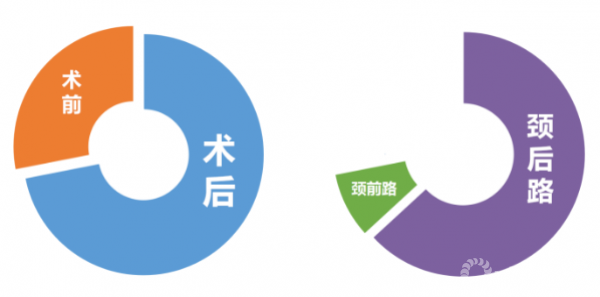

②轴性症状主要发生在颈椎后路术后,早期有研究表明后路单开门术后长期颈背痛的发生率甚至高达45%-80%。但同时有文献报道颈前路手术后亦可出现颈肩痛,并将这些颈肩痛也归结为轴性症状。

(五)不同入路对AS产生的独特影响

颈前路术后轴性症状:

颈前路椎间盘切除减压融合术术后早期颈肩部疼痛的原因与椎体间过度撑开有关,但随后会发生缓解。缓解原因:一方面,牵张感受器适应压力变化;另一方面,植骨界面的吸收可以降低椎间高度,相邻椎体终板的压力得以有效降低。

颈后路术后轴性症状:

常规后路单开门手术会对后方部分韧带复合体、双侧椎旁肌、部分棘突、棘间韧带、棘上韧带进行剥离或摘除,从而破坏维持颈椎生物力学的基本结构,影响颈椎结构的稳定性。故术后颈椎易发生生理曲度丢失,出现鹅颈畸形等并发症;另外由于手术创伤与组织缺损,术后发生广泛的结缔组织填充替代,出现广泛粘连,影响颈伸肌群功能及柔韧性。同时因肌肉附着点未重建,将导致不可恢复的肌肉萎缩,从而出现术后颈背部僵硬、酸胀、乏力、活动受限、活动受限等轴性症状。